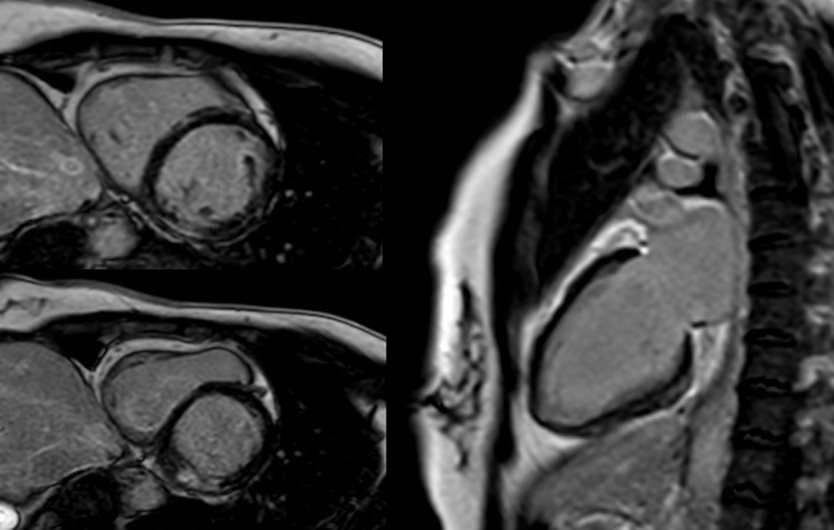

A cardiac magnetic resonance (CMR) performed on day 6 revealed a non-dilated, non-hypertrophic left ventricle with mildly reduced systolic function (LVEF 45%). Regional wall motion abnormalities involved the inferolateral basal and mid-segments and lateral apical wall. T2-weighted imaging demonstrated focal subepicardial hyperintensity in the inferolateral wall consistent with active edema. Late gadolinium enhancement (LGE) images revealed patchy subepicardial and mid-myocardial enhancement in matching territories, suggesting acute myocarditis. Additionally, there was focal wall thinning and festooning of the lateral wall (Figure 2).

Figure 2: CMR: LGE in inferolateral wall basal and mid-segments.